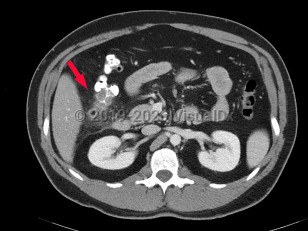

Diverticulitis is a disease characterized by inflammation in colonic diverticula. Cases are classified as uncomplicated or complicated on the basis of clinical and radiographic features. Uncomplicated cases are characterized by clinically stable patients with inflammation in a localized area of the bowel wall. By contrast, complicated disease is defined by the presence of abscess, phlegmon, fistula formation, obstruction (large bowel, small bowel), bleeding, perforation, or peritonitis, which are collectively present in about 12% of cases.